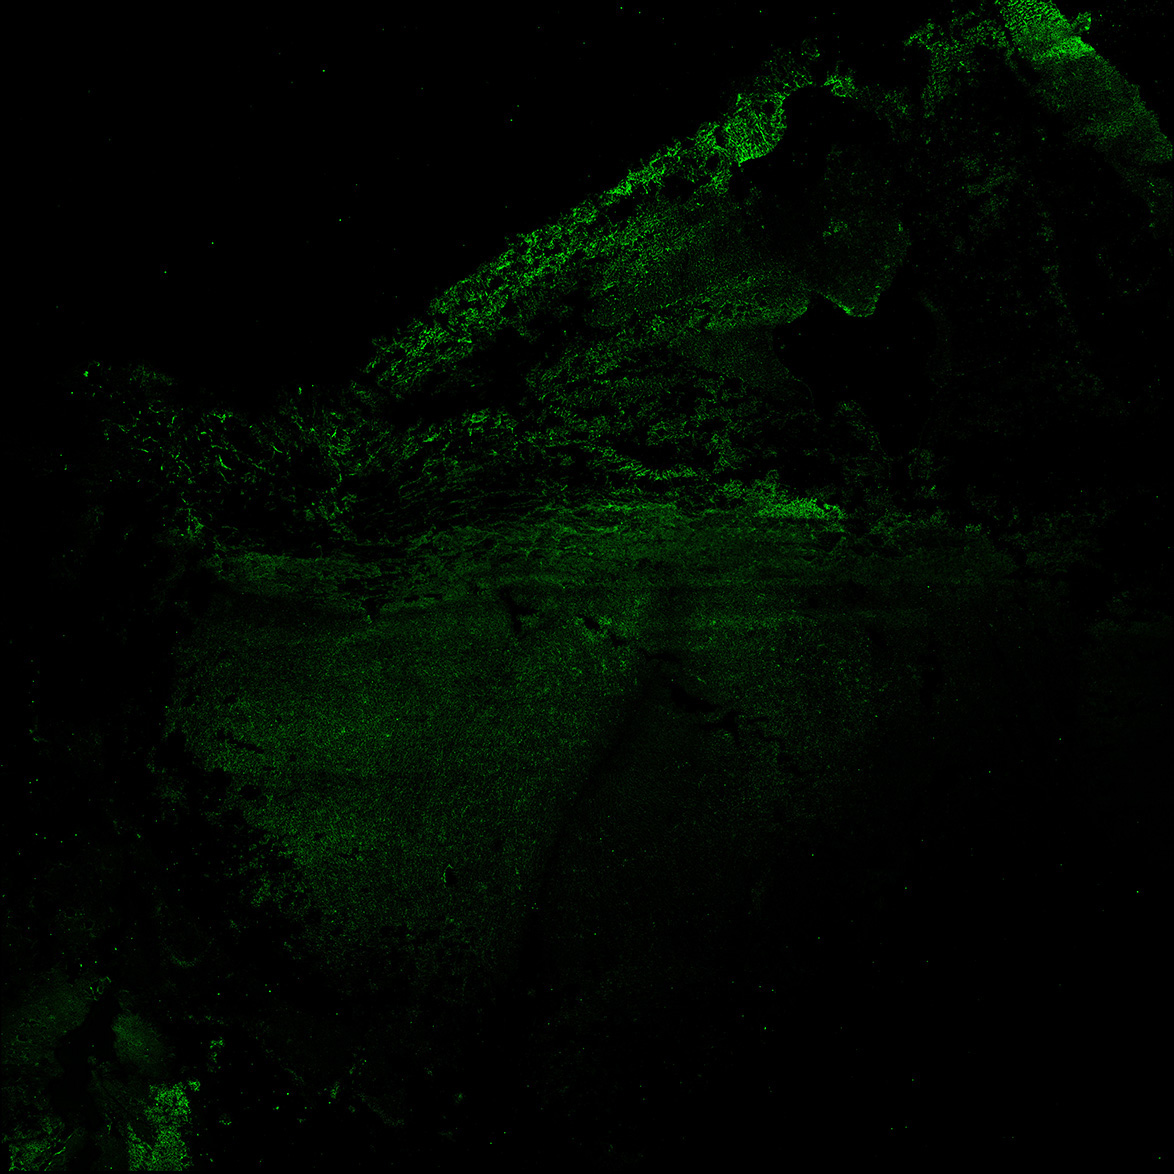

MAP2

11PCW human midbrain

SOX2

13PCW human midbrain

15PCW human midbrain

17PCW human midbrain

19PCW human midbrain

22PCW human midbrain